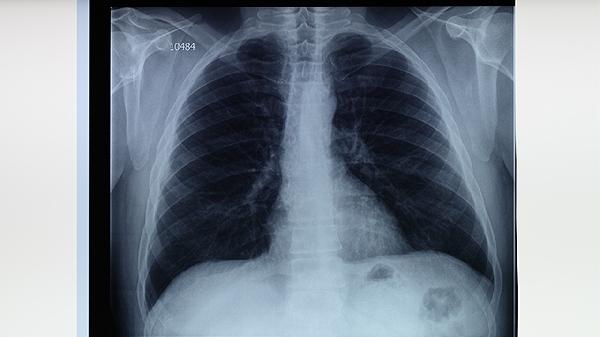

肺结核患者停药后应持续监测症状变化,每3-6个月复查胸部影像学及痰涂片检查。日常需保持均衡饮食,适当补充优质蛋白和维生素,避免过度劳累。居住环境应通风良好,减少与结核病患者的密切接触。若出现疑似复发症状,须立即就医进行痰培养和药敏试验,必要时调整治疗方案。